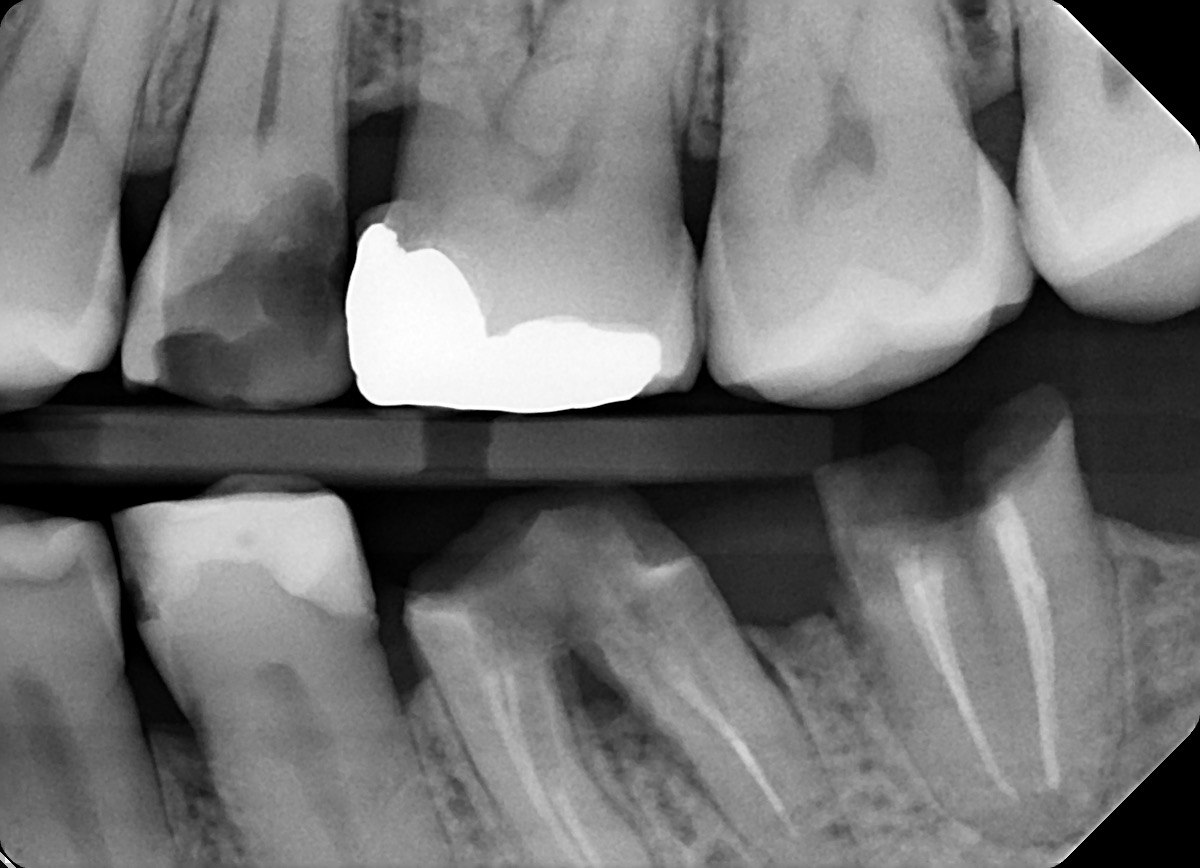

Question 1: What is the condition of the mesial surface of the tooth # 2.6?